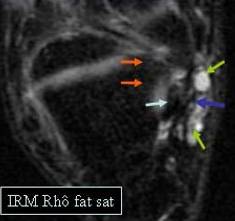

In IRM, exceptional indicat in aceasta patologie, arata un aspect

similar: cu doua semne suplimentare nevizualizate ecografic : participarea

ligamentului grasos infra patelar al lui HOFFA si o afectare

inflamatorie a medulairei osoase la nivelul patelei

In faza cronica, apar microcalcificari la nivelul entezei, care pot

preciza disparitia simptomelor. Se pot, de asemenea, gasi semnele complicatiilor sub forma de microchiste mai mult sau mai putin asociate cu o hiper vascularizatie anarhica